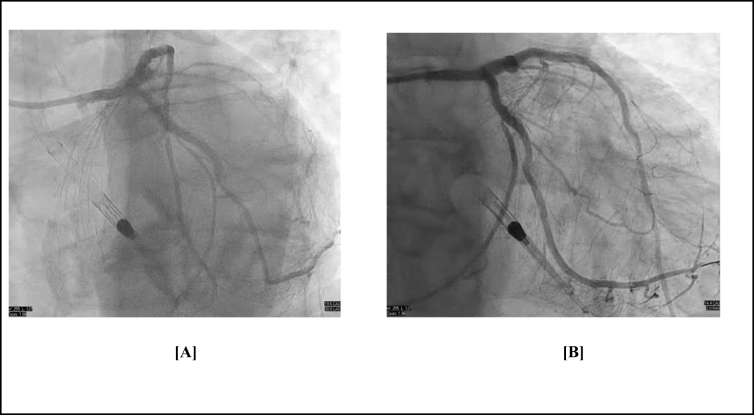

Case presentation: We present the case of a 68-year-old male with severe multivessel coronary artery disease with reduced left ventricular ejection fraction, and bilateral iliofemoral artery disease. Since there was difficulty in accessing the femoral arteries, axillary artery access was used to insert an Impella CP device to support high-risk PCI. The procedure involved successful revascularization of complex lesions using rotational atherectomy and stenting. The patient remained hemodynamically stable throughout and recovered without complications.